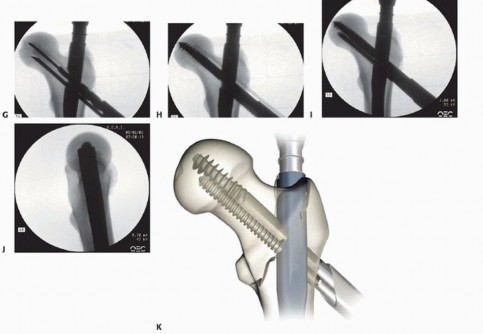

The derotation bar is inserted into the inferior hole to augment femoral head and neck stability during large lag screw reaming ( TECH FIG 7E,F). The surgeon confirms the length for the lag screw, subtracting 5 to 10 mm from the measured length for compression if desired. The 3.2-mm wire is overdrilled with the 10.5-mm cannulated drill, and the selected lag screw is inserted to within 5 mm of subchondral bone ( TECH FIG 7G). The derotation bar is removed and the compression gear drive screw is inserted through the guide. Traction is released from the leg and compression is started ( TECH FIG 7H-K). Compression through the gear drive does not begin until the head of the gear drive screw contacts the nail. Visualization of compression can be confirmed by C-arm and calibrations on the guide. Once compression is achieved, the screwdrivers are disassembled. Static locking of the screw assembly can be achieved with the integrated set screw within the nail. 398

TECH FIG 7 • Integrated screw cephalomedullary nail (InterTAN). A. Pilot drill hole for 3.2-mm wire for center-center position. B. AP radiograph with radiolucent alignment tower. C. Lateral radiograph with radiolucent guide centered over femoral head. D. Inferior screw hole for derotation bar and compression screw. E,F. Derotation bar inserted. G. Drill for cannulated center lag screw. H-J. Insertion of inferior compression screw and final AP and lateral views of integrated screws engaged. K. Schematic of integrated screws and nail in fracture. (K: Courtesy of Smith & Nephew, Inc., Memphis, TN.) 7. ##